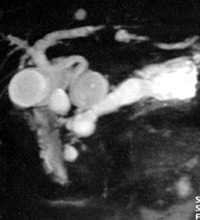

Η μαγνητική εντερόκλυση είναι μία πολλά υποσχόμενη μέθοδος για την απεικόνιση

των παθήσεων του λεπτού εντέρου. Από τη μέχρι τώρα κλινική εμπειρία προκύπτει

η μεγάλη διαγνωστική της αξία στη νόσο του Crohn, τα νεοπλάσματα του λεπτού

εντέρου και στην εντερική απόφραξη. Η μέθοδος είναι χρήσιμη για την παρακολούθηση

ασθενών με νόσο Crohn, απεικονίζει με εξαιρετική ευκρίνεια σημεία απόφραξης

και αποτυπώνει μικρά συρίγγια ή συριγγώδεις πόρους που δεν μπορούν να ανιχνευθούν

με ακρίβεια στη συμβατική εντερόκλυση (εικόνα 9).

ΕIKONA 9. Απεικόνιση εντερικού συριγγίου με α: συμβατική εντερόκλυση, β: μαγνητική

εντερόκλυση.